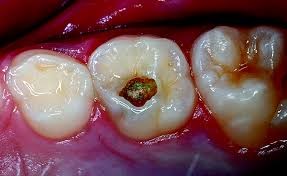

Для глубокого кариеса характерно наличие в зубе глубокой полости с пораженными микроорганизмами тканями, дно которой близко подходит к пульповой камере. В пульповой камере располагаются нервные окончания, воспалительный процесс оказывает воздействие на нервные волокна и зуб начинает болеть, реагируя на механические, химические и температурные манипуляции.

Отличительны симптомы при первичном и вторичном глубоком кариесе. Так, острая форма характеризуется узким входным отверстием в полость зуба и довольно широким основанием. Это делает больной зуб чувствительным к перепадам температур и химическим раздражителям (например, сладкой или кислой пище). Для хронической формы характерно широкое входное отверстие и узкое дно кариозной полости, поэтому основной дискомфорт человек испытывает при механическом воздействии на зуб (при зондировании, набивании пищи в кариозную полость, попытке самостоятельно извлечь остатки пищи).